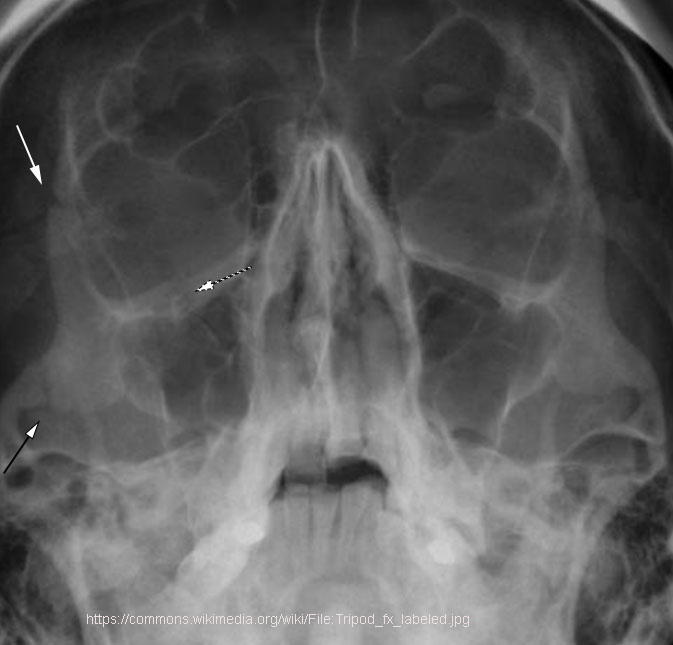

Which sites are involved in a tripod fracture?

Zygomatic arch, orbital floor/rim, and zygomatic-frontal suture.

What functional problem can a tripod fracture cause?

Chewing difficulty from temporalis muscle impingement.